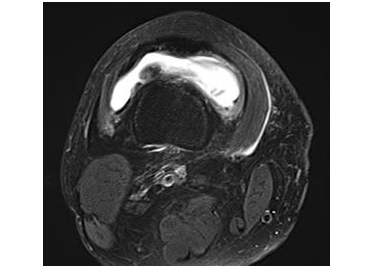

根据MRI影像,诊断为变形性膝关节病 等级4(末期)。

股骨内侧突发性骨坏死,半月板外周滑脱

白色部分膝盖股关节积液